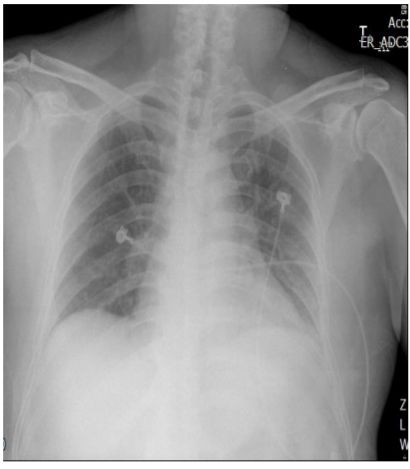

20. 一位65歲男性,有高血壓,糖尿病與B型肝炎合併肝硬 化病史.此次就診之主訴為靜止時喘不過氣來,且有端 坐呼吸與下肢水腫.過去4個月有乾咳,體重減輕5公斤 與倦怠感.體溫為攝氏37度,心跳為規則心律,每分鐘78 跳,呼吸為每分鐘17次.血壓為158/95毫米汞柱.胸部X 光呈現心臟擴大,胸部電腦斷層掃描呈現大量心包膜 積液.心包膜穿刺取心包膜液送檢後呈現如(附表). 3 天之後, 心包膜液adenosine deaminase 濃度為118.1 U/L (正常0.0~11.3 U/L).請問建議下列何者處置?